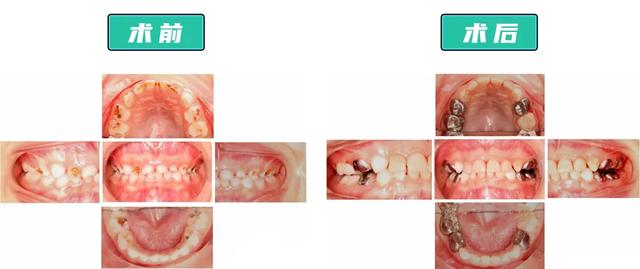

△密密麻麻的小黑牙和洞洞△

医生给童童没那么严重的前牙“套上”了透明树脂预成冠,针对要受力咀嚼、不太影响美观的后牙,“套上”了相对不易磨损脱落、可承受压力更大、性价比更高的金属预成冠。

整个过程治疗了17颗龋齿,做了12颗预成冠,一次性解决了童童的口腔问题。